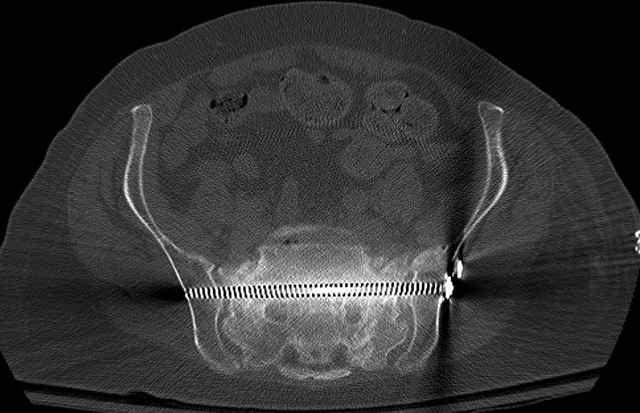

Here are a recent patient’s example slides...

3 Months After Fall

Continued Pain & Immobility

(+) Instability to Compressive Manual Exam

Pelvic CT Scan - 3 Months After Fall

Sacral Injuries

Ramus Fractures